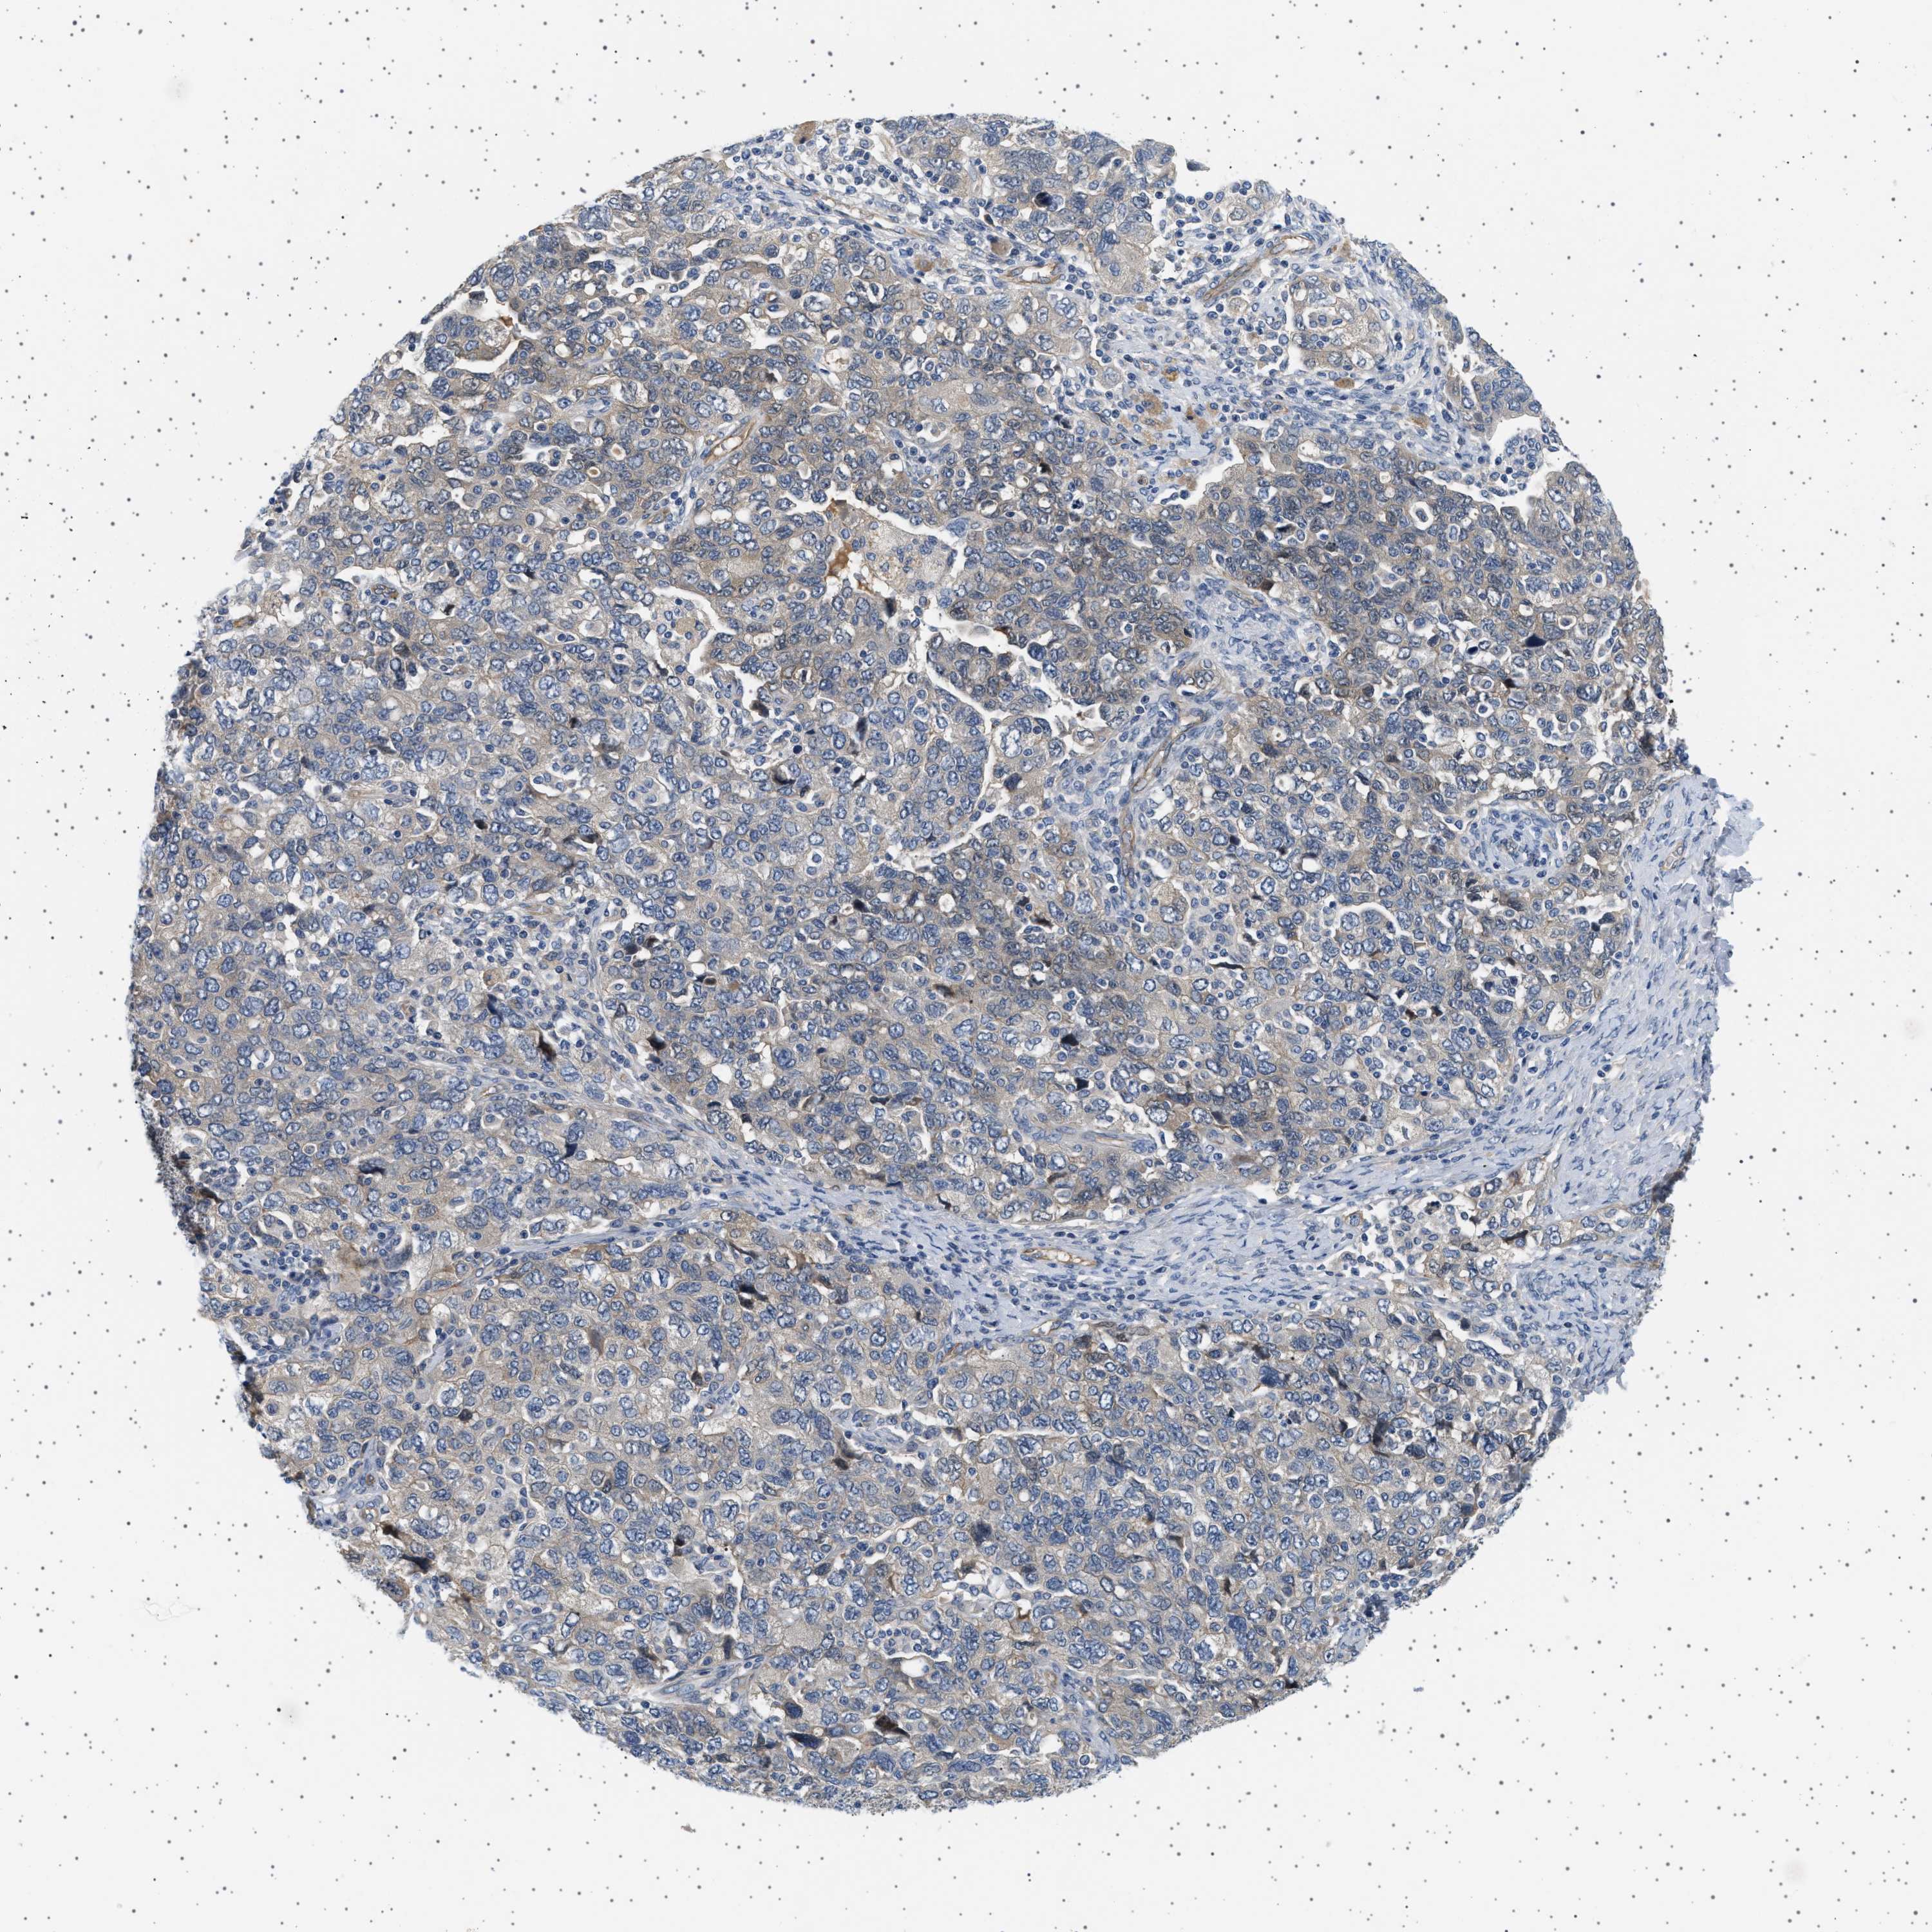

OVARIAN CANCER - Protein expressioni

A mouse-over function shows sample information and annotation data. Click on an image to view it in a full screen mode. Samples can be filtered based on level of antibody staining by selecting one or several of the following categories: high, medium, low and not detected. The assay and annotation is described here.

Note that samples used for immunohistochemistry by the Human Protein Atlas do not correspond to samples in the TCGA dataset.

Antibody stainingi

Antibody staining in the annotated cell types in the current human tissue is reported as not detected, low, medium, or high, based on conventional immunohistochemistry profiling in selected tissues. This score is based on the combination of the staining intensity and fraction of stained cells.

Each image is clickable and will lead to virtual microscopy that enables deeper exploration of all samples and also displays staining intensity scores, fraction scores and subcellular localization as well as patient and tissue information for each sample.

Antibody HPA018096

Staining

High

Medium

Low

Not detected

Intensity

Strong

Moderate

Weak

Negative

Quantity

>75%

75%-25%

<25%

None

Location

Nuclear

Cytoplasmic/membranous

Cytoplasmic/membranous,nuclear

Cystadenocarcinoma, serous, NOS

Carcinoma, endometroid

Cystadenocarcinoma, mucinous, NOS

Carcinoma, NOS